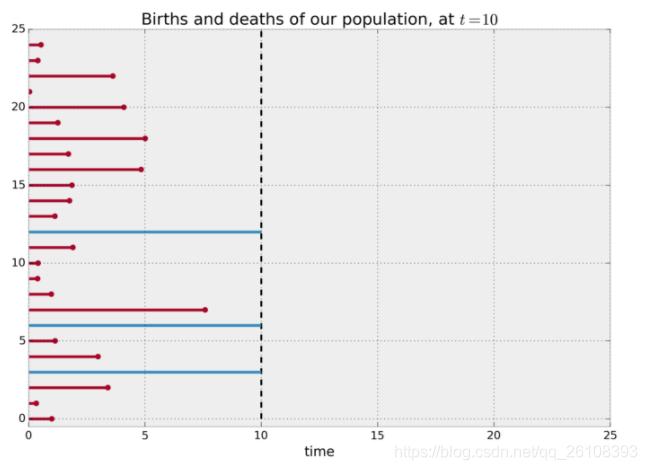

以样本的出生和死亡为例,我们观测一组样本的生存时间。然而我们观测和追踪他们是需要时间和金钱的成本的,不可能因为样本一直存活着,我们就一直将某个实验做下去。通常,专家只会对一组样本观测一段时间,例如,两年或者两个月。有些样本在观测期间触发了目标事件(death),而有些样本直到实验观测结束也没有触发目标事件,我们称没有触发目标事件的样本有右侧截断。

考虑这样一个例子:我们观测的目标人群实际上是来自两个不同的组(可以简单理解为患了不同的病),他们的平均存活时间是不一样的,假定A组的平均存活时间只有两个月,而B组的平均存活时间有十二个月。值得注意的是我们现在是把他们全部放在一起观测的,我们并不知道谁是A组谁是B组,而我们的目的是想知道这些人平均会活多久。 假定我们的实验进行了十个月就结束了。

如果我们只是简单地删除那些发生右侧截断的样本,然后对所有人的生存时间求平均,我们将会严重低估这个群体的生存时间。

如果我们不删除发生右侧截断的样本而直接求平均值,仍然会低估这个群体的平均生存时间,要注意的是,我们只能观测到10时刻之前的事情,10时刻之后的我们并不能看到。

上述例子是为了阐述方便所以让所有的样本的出生从0时刻开始,而实际上这是不必要的,生存分析并不要求所有样本在同一时刻出生,它只关注每个样本从出生到death触发或到实验结束之间的间隔时间,每个样本随时可以出生。